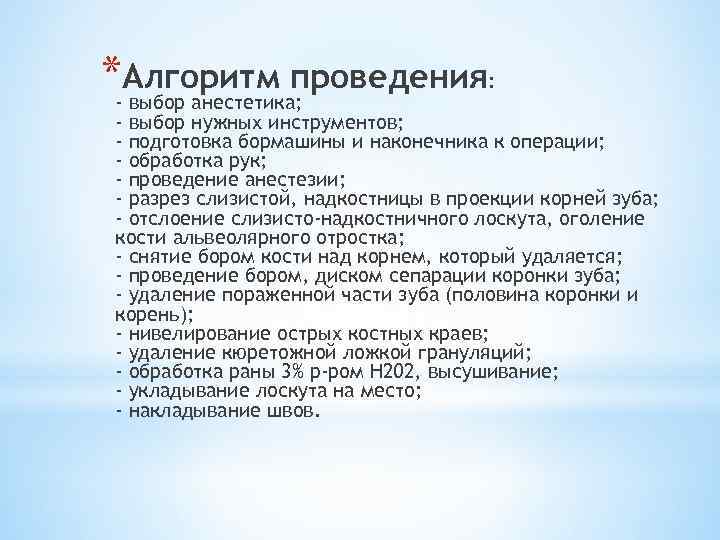

*-Алгоритм проведения: выбор анестетика; - выбор нужных инструментов; - подготовка бормашины и наконечника к операции; - обработка рук; - проведение анестезии; - разрез слизистой, надкостницы в проекции корней зуба; - отслоение слизисто-надкостничного лоскута, оголение кости альвеолярного отростка; - снятие бором кости над корнем, который удаляется; - проведение бором, диском сепарации коронки зуба; - удаление пораженной части зуба (половина коронки и корень); - нивелирование острых костных краев; - удаление кюретожной ложкой грануляций; - обработка раны 3% р-ром Н 202, высушивание; - укладывание лоскута на место; - накладывание швов.

*-Алгоритм проведения: выбор анестетика; - выбор нужных инструментов; - подготовка бормашины и наконечника к операции; - обработка рук; - проведение анестезии; - разрез слизистой, надкостницы в проекции корней зуба; - отслоение слизисто-надкостничного лоскута, оголение кости альвеолярного отростка; - снятие бором кости над корнем, который удаляется; - проведение бором, диском сепарации коронки зуба; - удаление пораженной части зуба (половина коронки и корень); - нивелирование острых костных краев; - удаление кюретожной ложкой грануляций; - обработка раны 3% р-ром Н 202, высушивание; - укладывание лоскута на место; - накладывание швов.